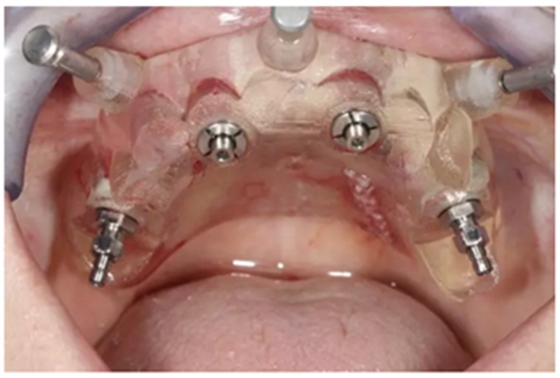

通過固位釘固定上頜NobelGuide外科導(dǎo)板和第一枚已植入的植體和導(dǎo)板基臺。

4枚NobelReplace CC RP4.3植體(11.5mm 軸向植體和13mm 傾斜植體)已植入完成:前牙區(qū)植體上裝配的是導(dǎo)板基臺,后牙傾斜植體上裝配的是內(nèi)錐形連接的引導(dǎo)式持釘器。

使用內(nèi)錐形連接引導(dǎo)式持釘器在下頜前牙區(qū)植入NobelReplace CC植體。

4枚NobelReplace CC植體均已植入完成:前牙區(qū)植入NP 3.5*13mm植體并裝配引導(dǎo)式基臺以固定導(dǎo)板,后牙區(qū)植入RP4.3*16mm植體并裝配內(nèi)錐形連接引導(dǎo)式持釘器。